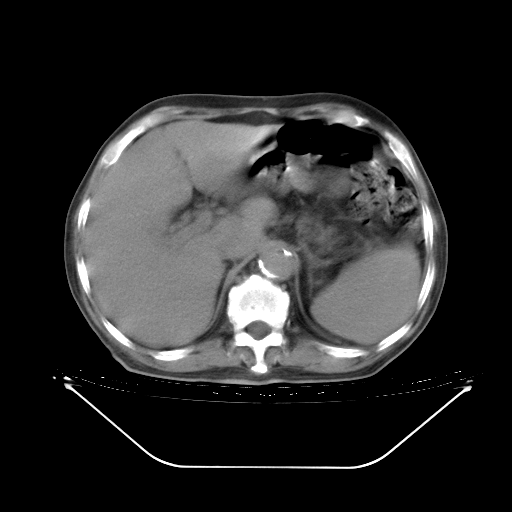

5月9日肺部CT(在4月27日齐鲁医院肺部CT描述部分肺组织磨玻璃样改变,12天后肺组织广泛磨玻璃样改变)

2009年5月9日肺部CT

大致读了系列胸部CT:纵隔窗无明显异常,肺窗:从4、27至今:主要是双肺中下野外带可见毛玻璃样改变,目前处于急性肺泡炎阶段,至于原因考虑1、结替组织或胶原血管性疾病所致?2、恶性疾病如恶组在肺部所致的表现或细支气管肺泡癌?3、药物或其它原因如肺蛋白沉着症所致肺泡炎目前不太可能?总之,明天就去请我院的呼吸科、感染科、血液科和临免专家会诊哈。